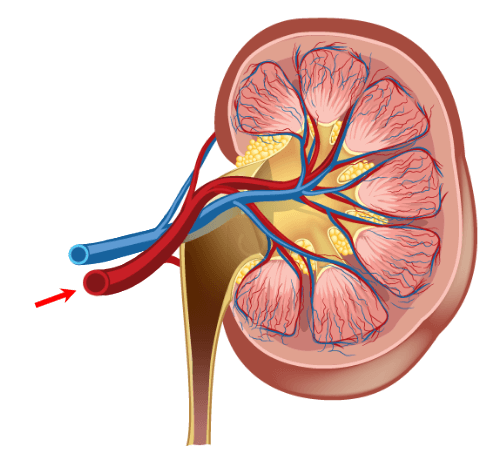

When discussing contrast agents, one must have a full appreciation of the benefits, which we have already discussed, but also the risks. The biggest risk of Gadolinium-based contrast agents is NSF or Nephrogenic systemic fibrosis. Which we will discuss in a few minutes. At present, the only measure that can predict a possible outcome of NSF is the renal function. This involves a simple blood test, which can be done in a doctor’s office or clinic, just a few minutes to a few days before the MRI. We look at the patient’s Creatinine and GFR.

Kidney Function

Kidney function is important to measure when injecting Gadolinium (and some other IV contrasts). It is imperative that the kidneys be working well enough to take the contrast agents out of the bloodstream quickly, usually within 24 hour period. When Gadolinium stays in the bloodstream too long, it will deposit in the tissue and may lead to a condition called NSF, which we will discuss later on.

The kidney function is measured with a simple blood test. The BUN or Blood Urea Nitrogen is measured This will tell how well hydrated the kidneys are. A normal range for BUN is 17-25. The next number is creatinine. The creatine tells us how well the kidney function or how efficiently they are removing excess creatine from the blood. A normal creatinine level is 0.7-1.6.

Always be sure to check the serum creatinine, not the urine creatinine which is expected to be much higher. Lastly, we evaluate the GFR or eGFR because it is estimated. The GFR is the Glomerular Filtration Rate. This number is considered to be more accurate than just a Creatinine because it takes other factors such as age, sex, and ethnicity into consideration. A normal GFR would be anything over 60. On a young healthy adult, it is around 100. Usually, about 60, a result is given>60. One would be concerned about injecting Gadolinium in a patient with a GFR less than 60, and usually, no injection occurs if it is below 30.